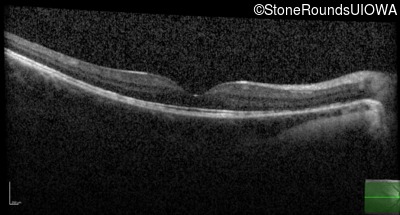

Optical Coherence Tomography - Right - 20/40 +1

Exemplar / OCT Stack